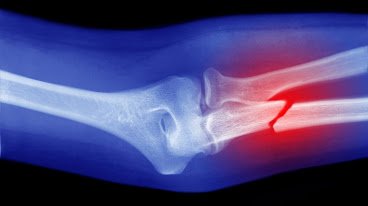

6. Bone Fractures

If you’ve suffered a bone fracture, an orthopedic doctor ensures proper alignment and healing, reducing the risk of long-term complications.